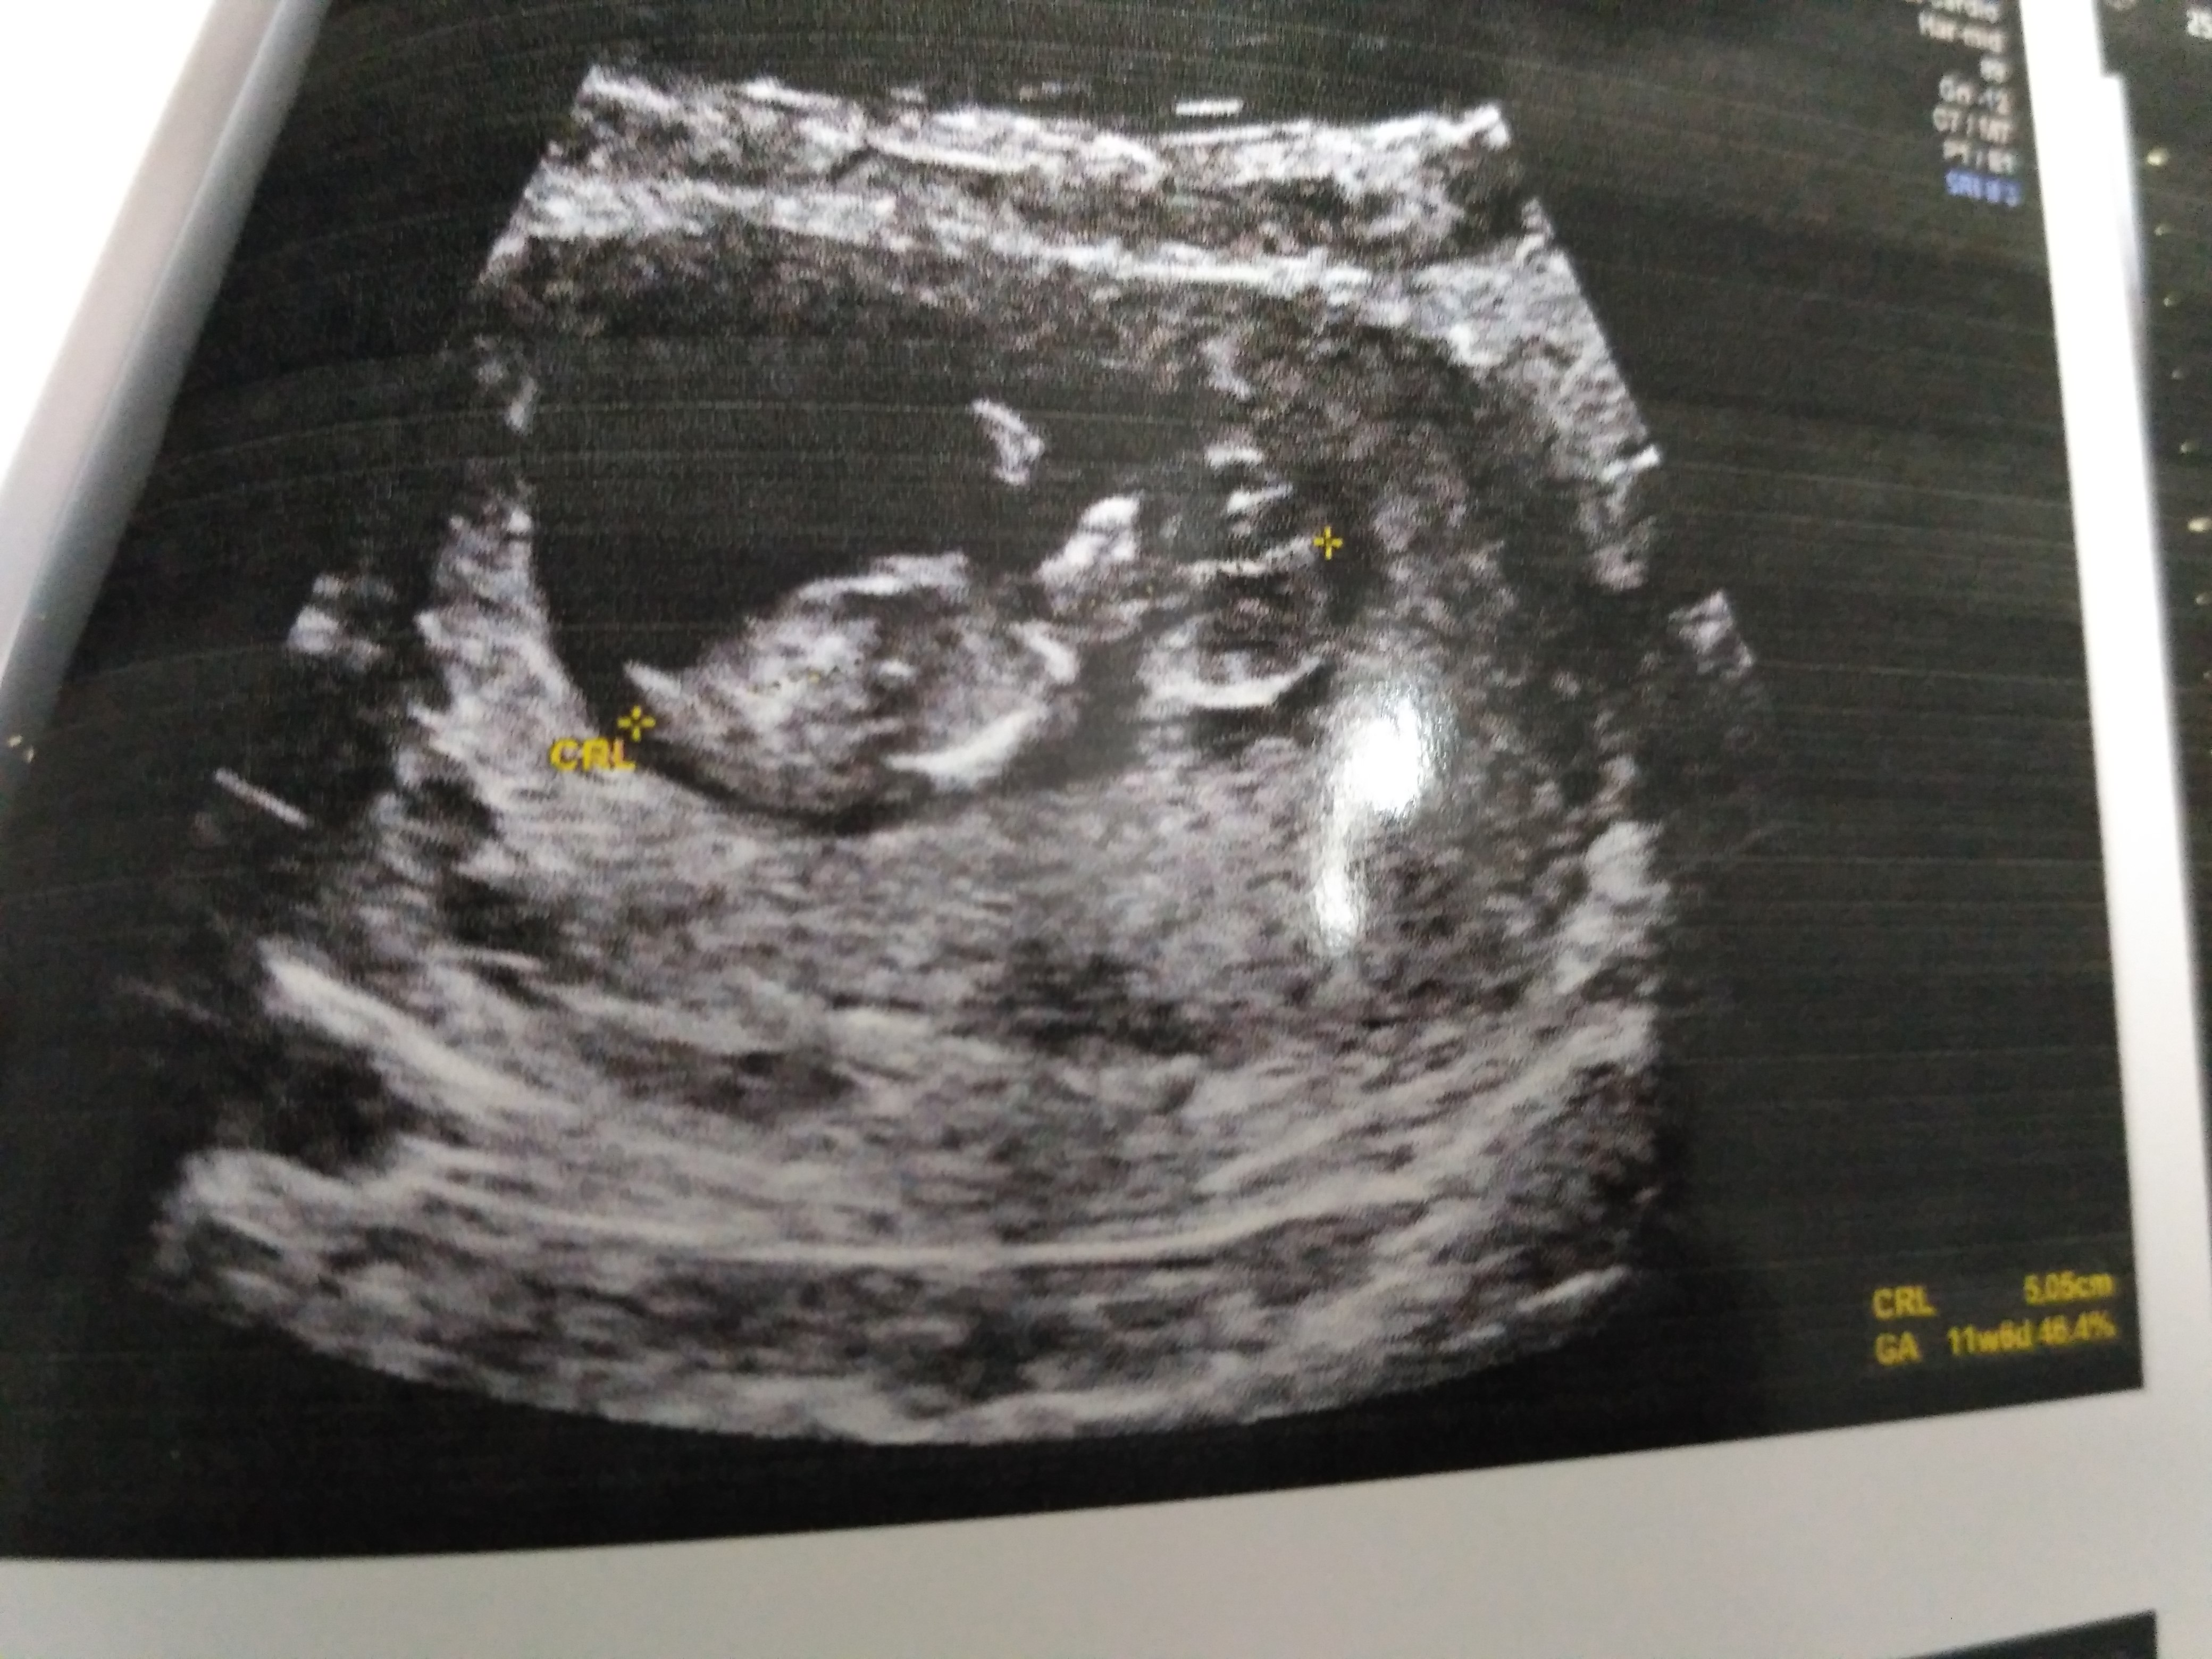

This is my 11w5d scan pic.. pls guess the gender by nub theory!Attachment 39879